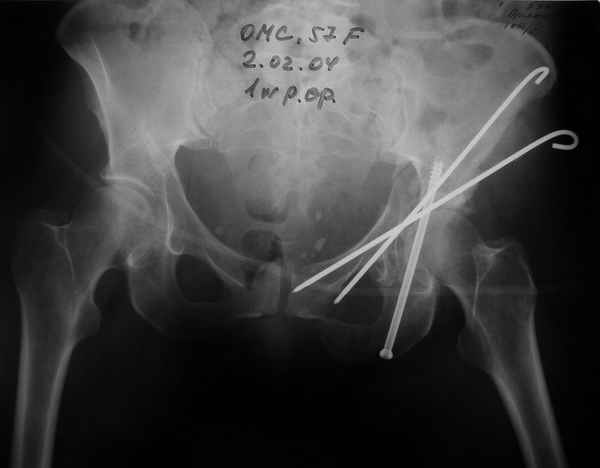

02.02.04